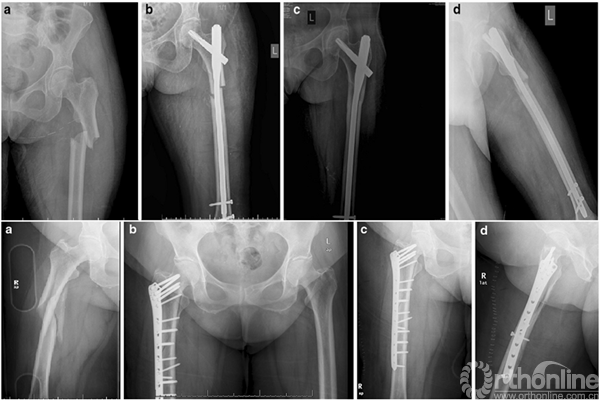

邓XX,男,56岁

术后8周

1.进针点错误导致髋内翻和固定失败;

2.辅助捆绑带或阻挡钉能增加骨折稳定性促进愈合;

3.骨折近端头颈的不稳导致髓内钉固定的失败;

4.正确的进针点和足够的髓内钉长度,即使不能达到解剖复位,也能收到满意的愈合结果;

5.内侧粉碎和钢板远端螺钉数量不足是失败原因之一;

6.长阶段劈裂骨折非解剖复位反而增加骨痂量收到满意效果。